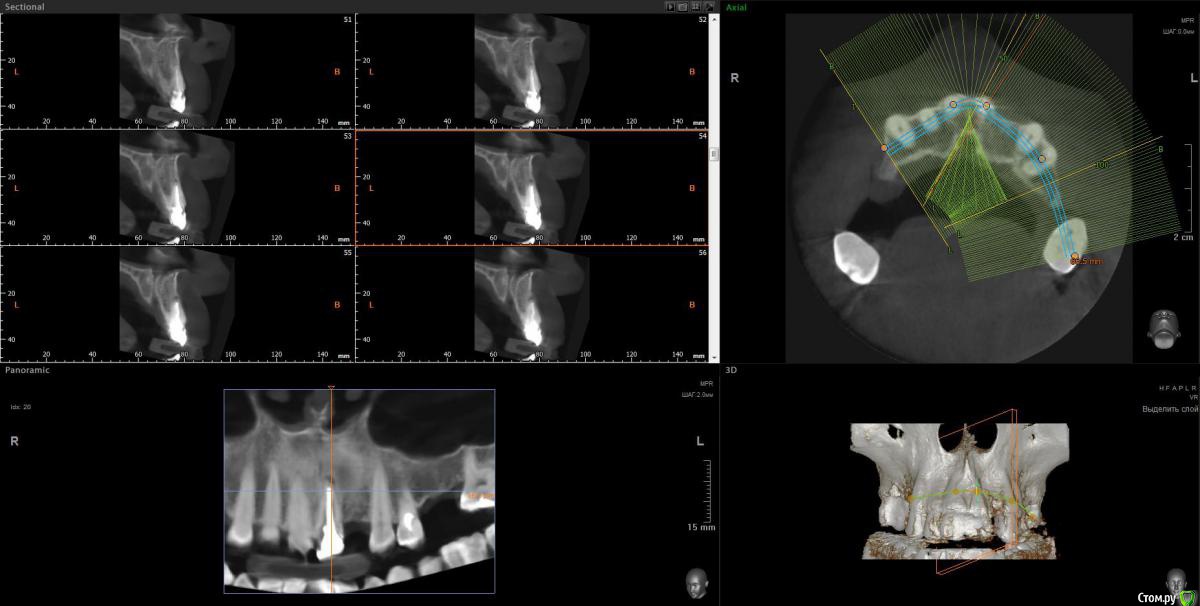

Просьба ко всем не равнодушным! Глянуть КТ верхней челюсти, 27 зуб  и место где удалили 16, может ещё где-то могут быть проблемы.  На фото видно где покраснение на дёснах, в этих местах возникают боли при движении головой. Бывает боль слева если засыпаю на левой стороне. Набуханий или флюсов нигде не видно.Прошу делиться мнениями, для меня это очень - очень важно. Стоматолог визуальных проблем на месте удалённого зуба не видит, всё зажило.

По данным КТ в зоне удалённого зуба 16 ничего особенного, разве что, ретенированный (непрорезавшийся) зуб 18.

Зуб 27 требует внимания, необходим очный осмотр.

Также стоит обратить внимание на зубы 21 и 24